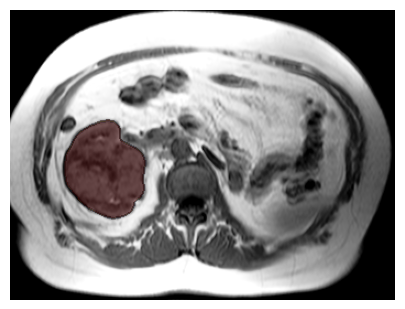

Purpose: To introduce a deep learning model capable of multi-organ segmentation in MRI scans, offering a solution to the current limitations in MRI analysis due to challenges in resolution, standardized intensity values, and variability in sequences. Materials and Methods: he model was trained on 1,200 manually annotated MRI scans from the UK Biobank, 221 in-house MRI scans and 1228 CT scans, leveraging cross-modality transfer learning from CT segmentation models. A human-in-the-loop annotation workflow was employed to efficiently create high-quality segmentations. The model's performance was evaluated on NAKO and the AMOS22 dataset containing 600 and 60 MRI examinations. Dice Similarity Coefficient (DSC) and Hausdorff Distance (HD) was used to assess segmentation accuracy. The model will be open sourced. Results: The model showcased high accuracy in segmenting well-defined organs, achieving Dice Similarity Coefficient (DSC) scores of 0.97 for the right and left lungs, and 0.95 for the heart. It also demonstrated robustness in organs like the liver (DSC: 0.96) and kidneys (DSC: 0.95 left, 0.95 right), which present more variability. However, segmentation of smaller and complex structures such as the portal and splenic veins (DSC: 0.54) and adrenal glands (DSC: 0.65 left, 0.61 right) revealed the need for further model optimization. Conclusion: The proposed model is a robust, tool for accurate segmentation of 40 anatomical structures in MRI and CT images. By leveraging cross-modality learning and interactive annotation, the model achieves strong performance and generalizability across diverse datasets, making it a valuable resource for researchers and clinicians. It is open source and can be downloaded from https://github.com/hhaentze/MRSegmentator.